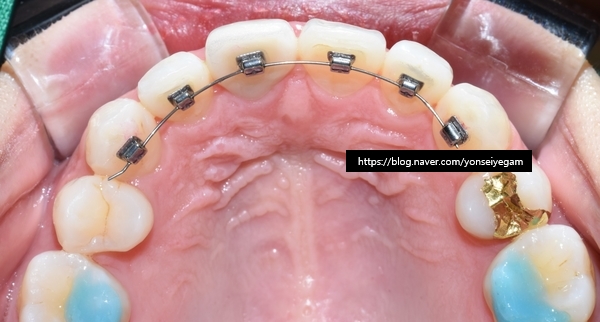

이렇게 말이죠. 위 사진의 환자분의 아래쪽 치아입니다.

다른 치과에서 교정이 끝나고 아래쪽만 유지장치를 붙이고 위쪽은 안붙이셨나봐요.

그래서 이 환자분의 경우

보이지 않는 방식으로 교정을 원하셨기 때문에

보이지 않게 설측에 붙이는 티끌교정으로 진행하였습니다.

치아안쪽에 장치를 부착하기 때문에 겉에서는 보이지 않습니다.